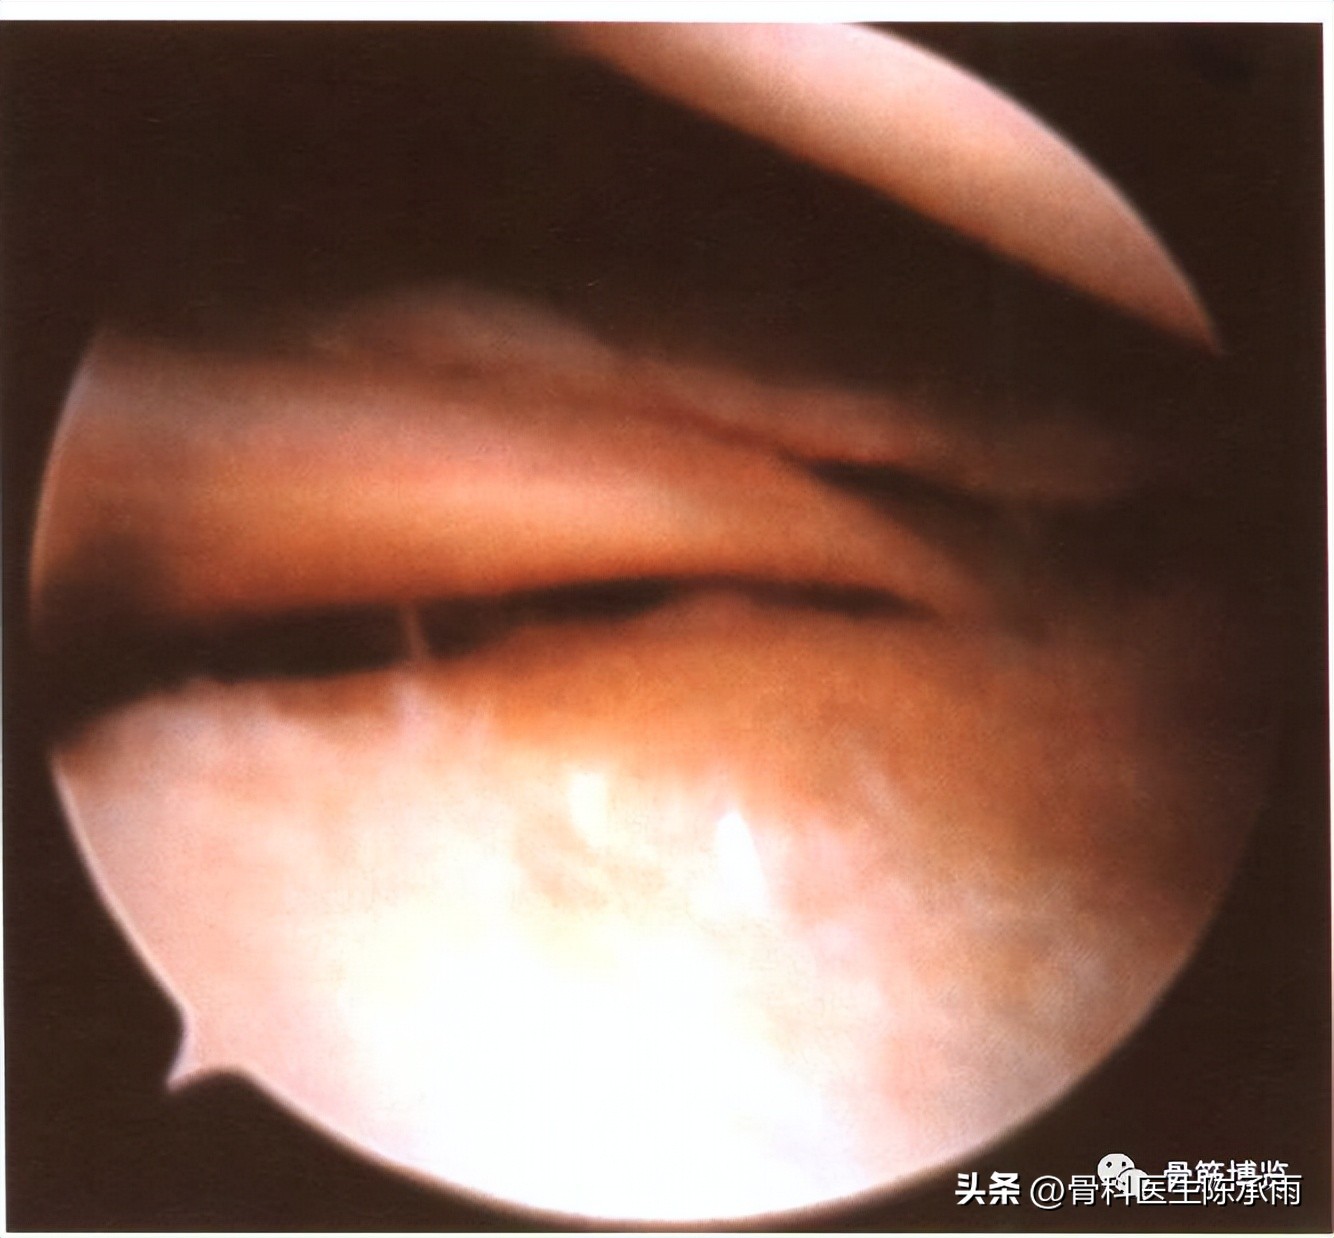

(二)水平裂

是指半月板的裂口与半月板表面相平行的撕裂。在成人及上年纪的人中较常见。多见于内侧半月板的体后部和外侧半月板的体部。大部分活瓣状撕裂和复合裂即由层裂发展而来。盘状软骨损伤中更为多见,有的可向上或向下通向关节,有的则仅为单纯的层裂。